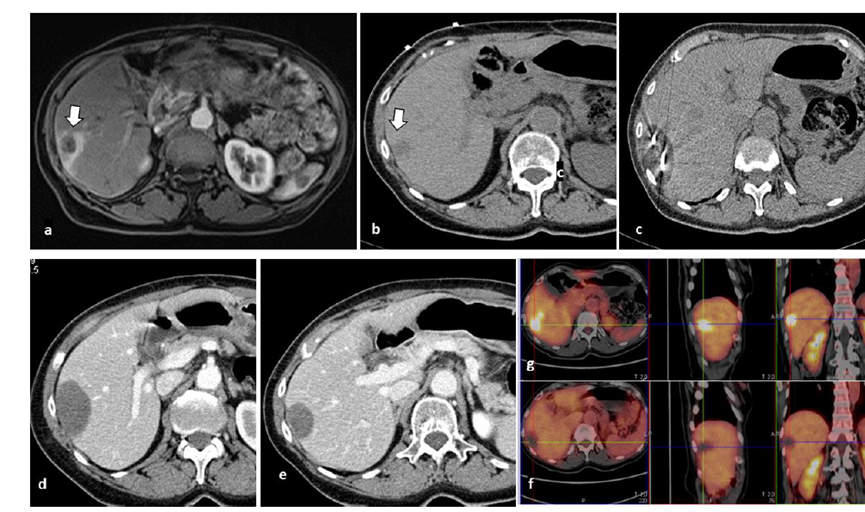

79 岁男性,肝转移(结直肠癌)肿瘤的完全消融病例

( a ) 轴向 MRI 和 ( b ) 轴向 CT 显示肝S8段有一个16mm的病灶,邻近肝缘。

( c )冷冻消融期间CT显示放置了2个冷冻探针,低密度冰球包围病灶。

(d)术后1个月随访 CT显示冰球对应的坏死区域,未见复发。

(e)术后6个月的CT,坏死区域缩小,未见复发。

(f)与基线影像(g)相比,12个月后的FDG-PET/CT显示未见FDG摄取。

62岁女性,肝转移(卵巢癌)肿瘤的完全消融病例

(a)轴向CT显示病变位置毗邻心脏和上腔静脉(黑色箭头)。

(b)术中轴向CT扫描:使用三个冷冻探针。

(c)冠状面和(d)矢状面显示冰球毗邻心包。

1个月后的轴向(e)和冠状位(f)增强CT扫描显示低密度区域,由于肉芽组织反应引起的边缘增强。